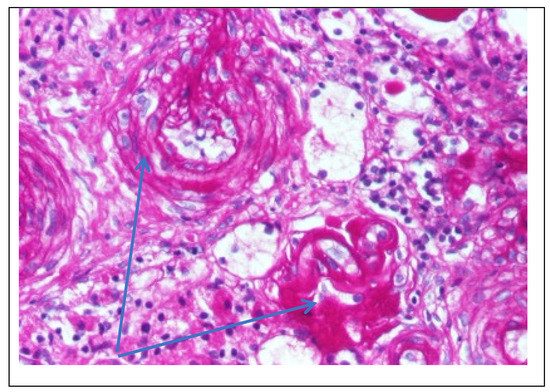

Figure 4. Kidney biopsy (PAS staining × 200)—Fibrinoid deposits in the glomerulus and PAS+ wall thickened vessel (blue arrow).

Rare glomeruli with fibrinoid deposits in the mesangium and outstanding endothelial cells with a swollen appearance are observed (Figure 4)

Following the evaluations for the etiology of end stage renal disease (ESRD) we recommended abdominal ultrasound and CT scan. The abdominal ultrasound showed multiple homogenous hyperechoic nodular formations. The CT scan showed expansive renal formations replacing renal parenchyma, with a mass effect on it (Figure 2). We thought in that moment of a bilateral nephroblastoma, but the clinical and biological dates excluded it. There remained a possibility of extrapulmonary renal tuberculosis (due to his personal and family history). Even if the culture was negative for Koch Bacillus, while a value of 22 mm Palmer III—suggests tuberculin turn, the treatment was initiated according to the international guidelines [6] by the phthisiologist: triple combination of isoniazid, rifampicin and pyrazinamide in doses adjusted to his clearance, in the 7/7 scheme for 2 months, then isoniazid and rifampicin in the same doses 7/7 for another 7 months [6]. Two months after the initiation of the tuberculostatic treatment, a CT reevaluation was performed, which showed no changes in the renal formations, although biologically the inflammatory syndrome was absent. The child continued the chronic dialysis program and still had important palm-plant pain burning type. The suspicion of chronic glomerulonephritis with evolution towards end-stage renal failure remained, so, we decided to perform the kidney biopsy who showed Chronic glomerulonephritis with segmental and diffuse glomerular hyalinization (Table 1, Figure 3, Figure 4, Figure 5 and Figure 6).

Children with Fabry disease generally do not develop chronic kidney disease until adulthood, when renal failure accounts for much of the morbidity and mortality associated with this disease, particularly in males. Globotriaosylceramide accumulation in renal cells and effacement of podocyte processes can be seen in renal biopsies in children with Fabry disease, even before proteinuria manifests as an early sign of renal involvement [18,20]. In this situation the kidney biopsy with electron microscopy is mandatory to make a differential diagnosis between minimal change nephrotic syndrome and podocyte involvement in context of Fabry disease. In nephrotic syndrome found in electron microscopy the retraction of podocyte processes inside the cell body, with the appearance of a flat epithelial layer [21]. Renal biopsy has been proposed and shown to be safe by several authors and should be considered in selected pediatric cases, especially when the decision to start renal replacement therapy is questionable or in children with significant proteinuria where renal biopsy is essential to rule out a second kidney disease, such as in our case. Focal segmental glomerulosclerosis (FSGS) is a form of glomerulonephritis that develops in various kidney lesions. Because a renal biopsy is not routinely performed especially in proteinuria in the nephrotic range, rigorous estimation of the incidence of FSGS in children is hindered [22]. In our case, the child presented with nephritic-range proteinuria and severe renal failure, so we performed a renal biopsy that revealed chronic glomerulonephritis with segmental and diffuse glomerular hyalinization (sclerosis). Only after the biopsy of the lymph nodes did I find the final diagnosis.